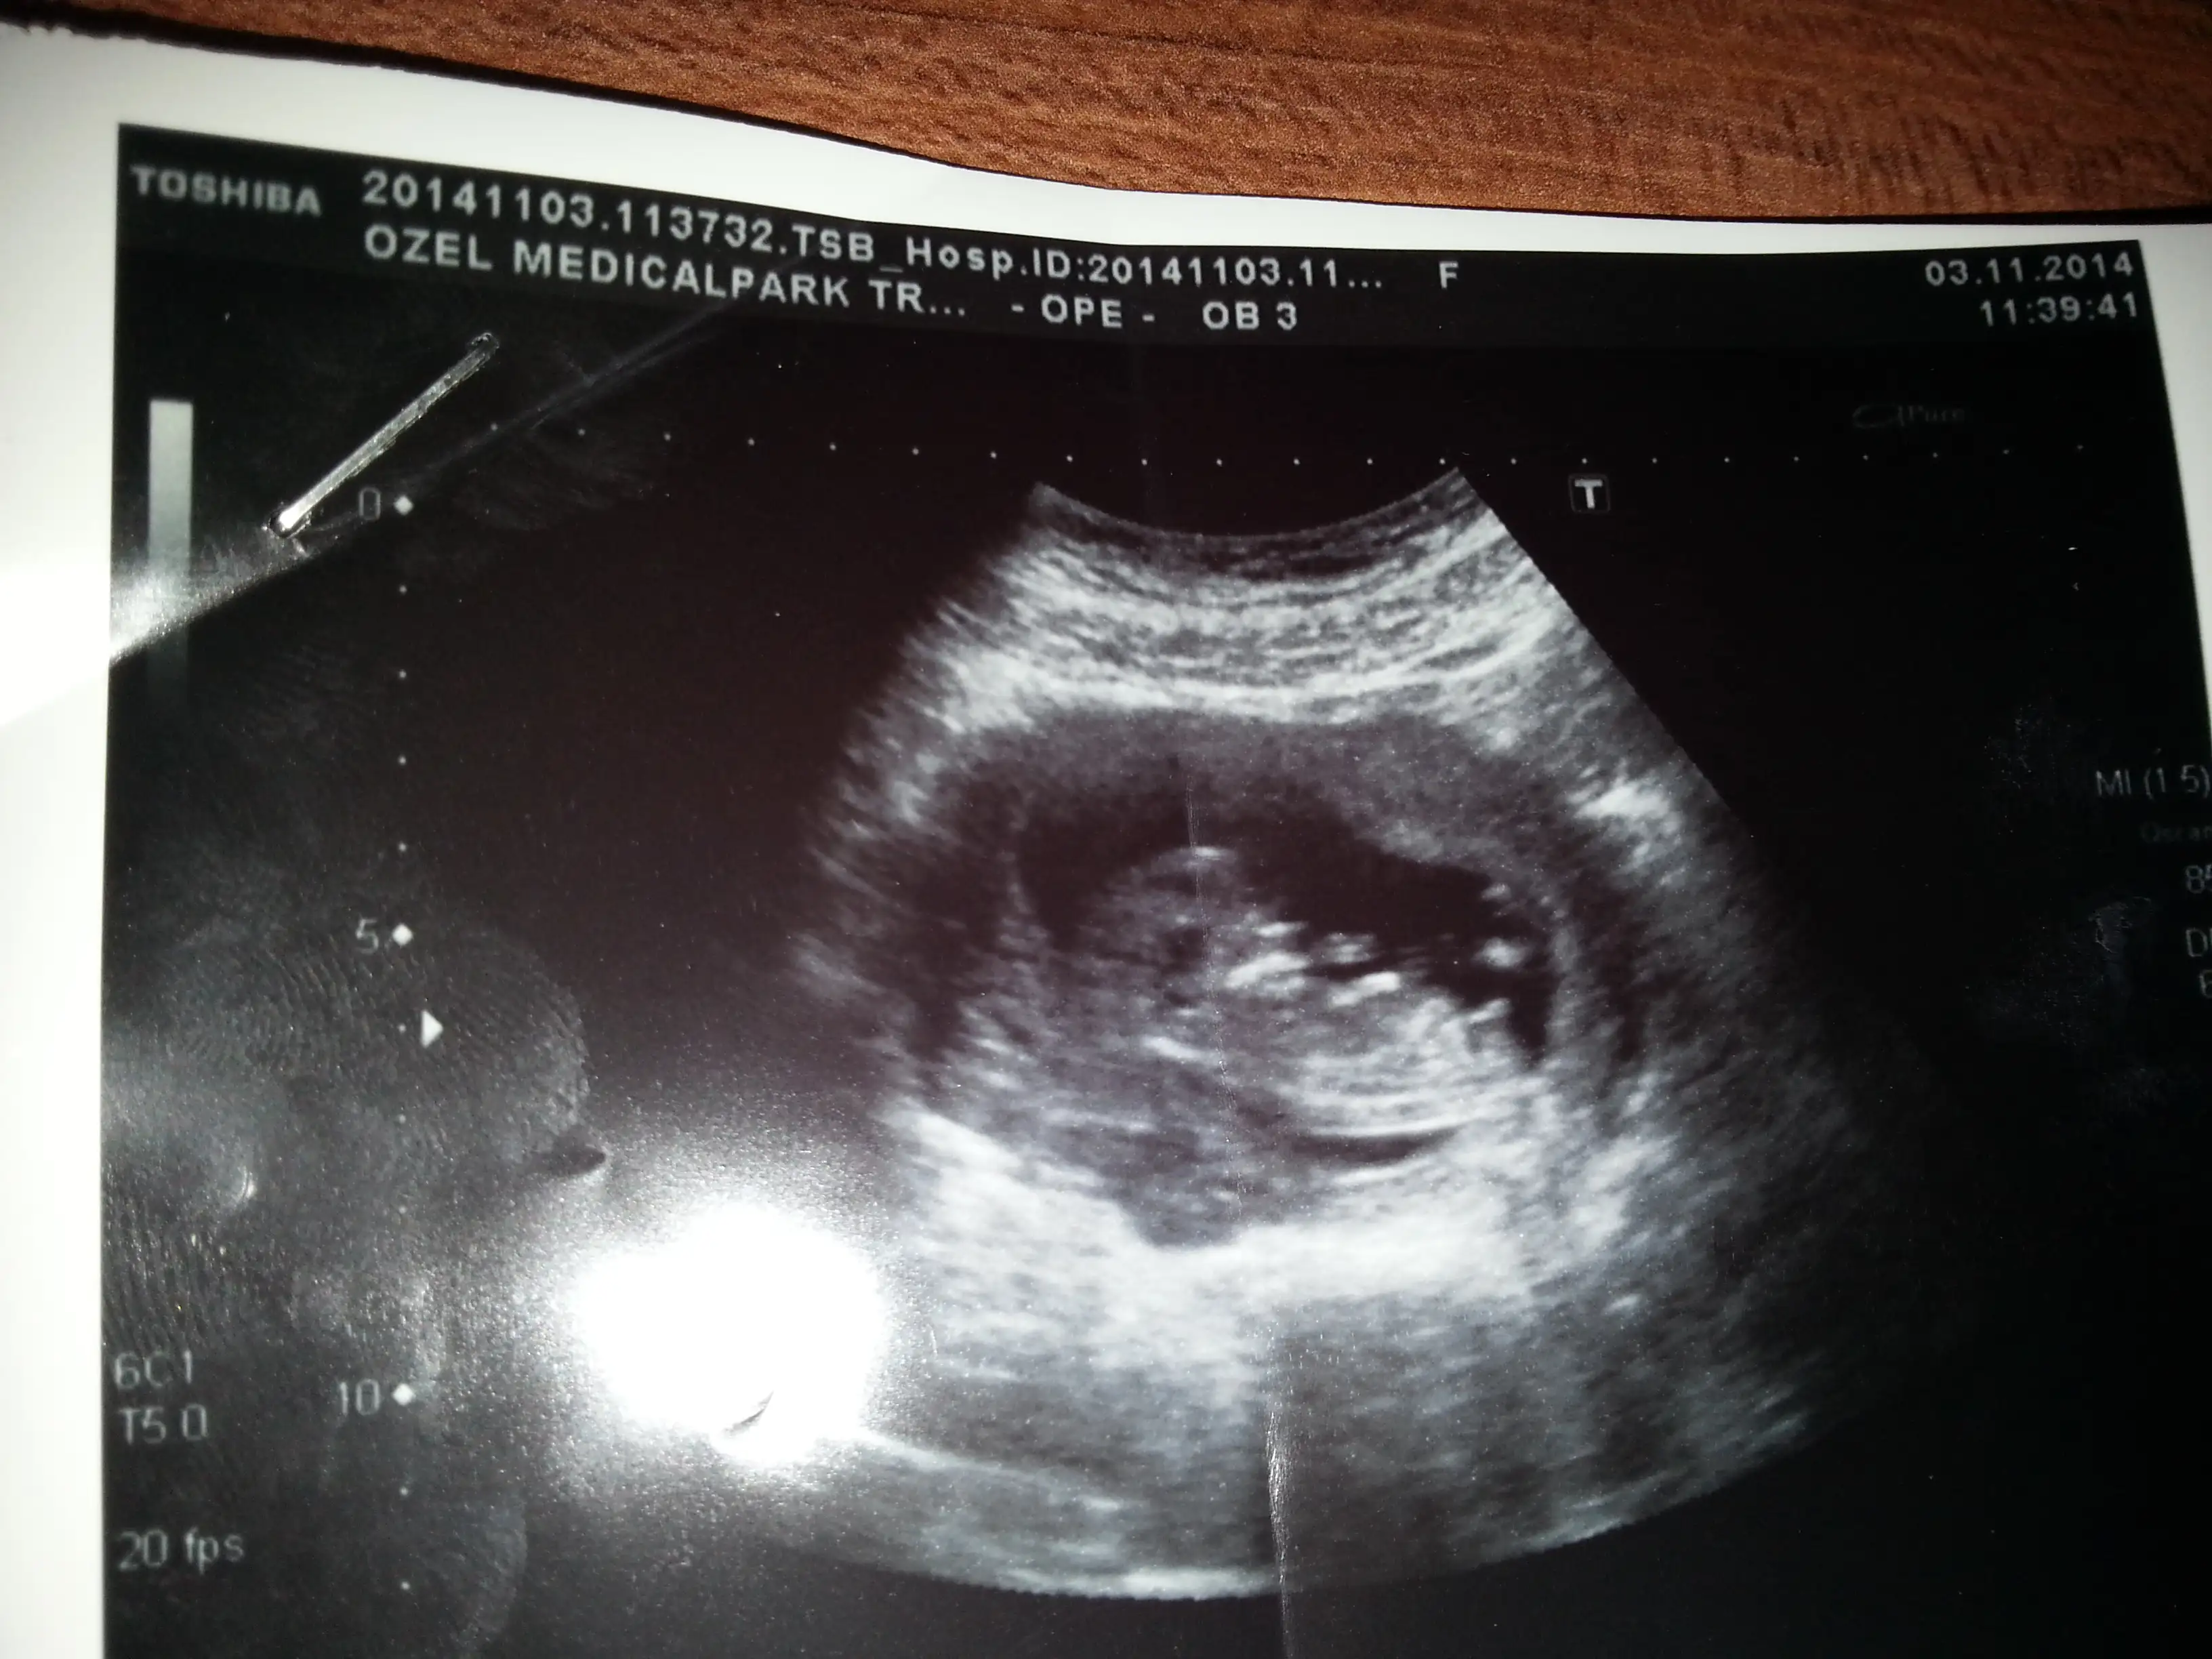

dr soylemeden siz gorun genital nub teorisi ( bebegin cinsiyeti)

Nubu iyi gordugum surece yorumu iyi yaparim:KK53:Canim ben ankaradayim zekai tahire gidiyorum varmi ultrason foton

Merhaba bunlardan cinsiyet tahmini yapılabilir mi. Tahmininiz var mi